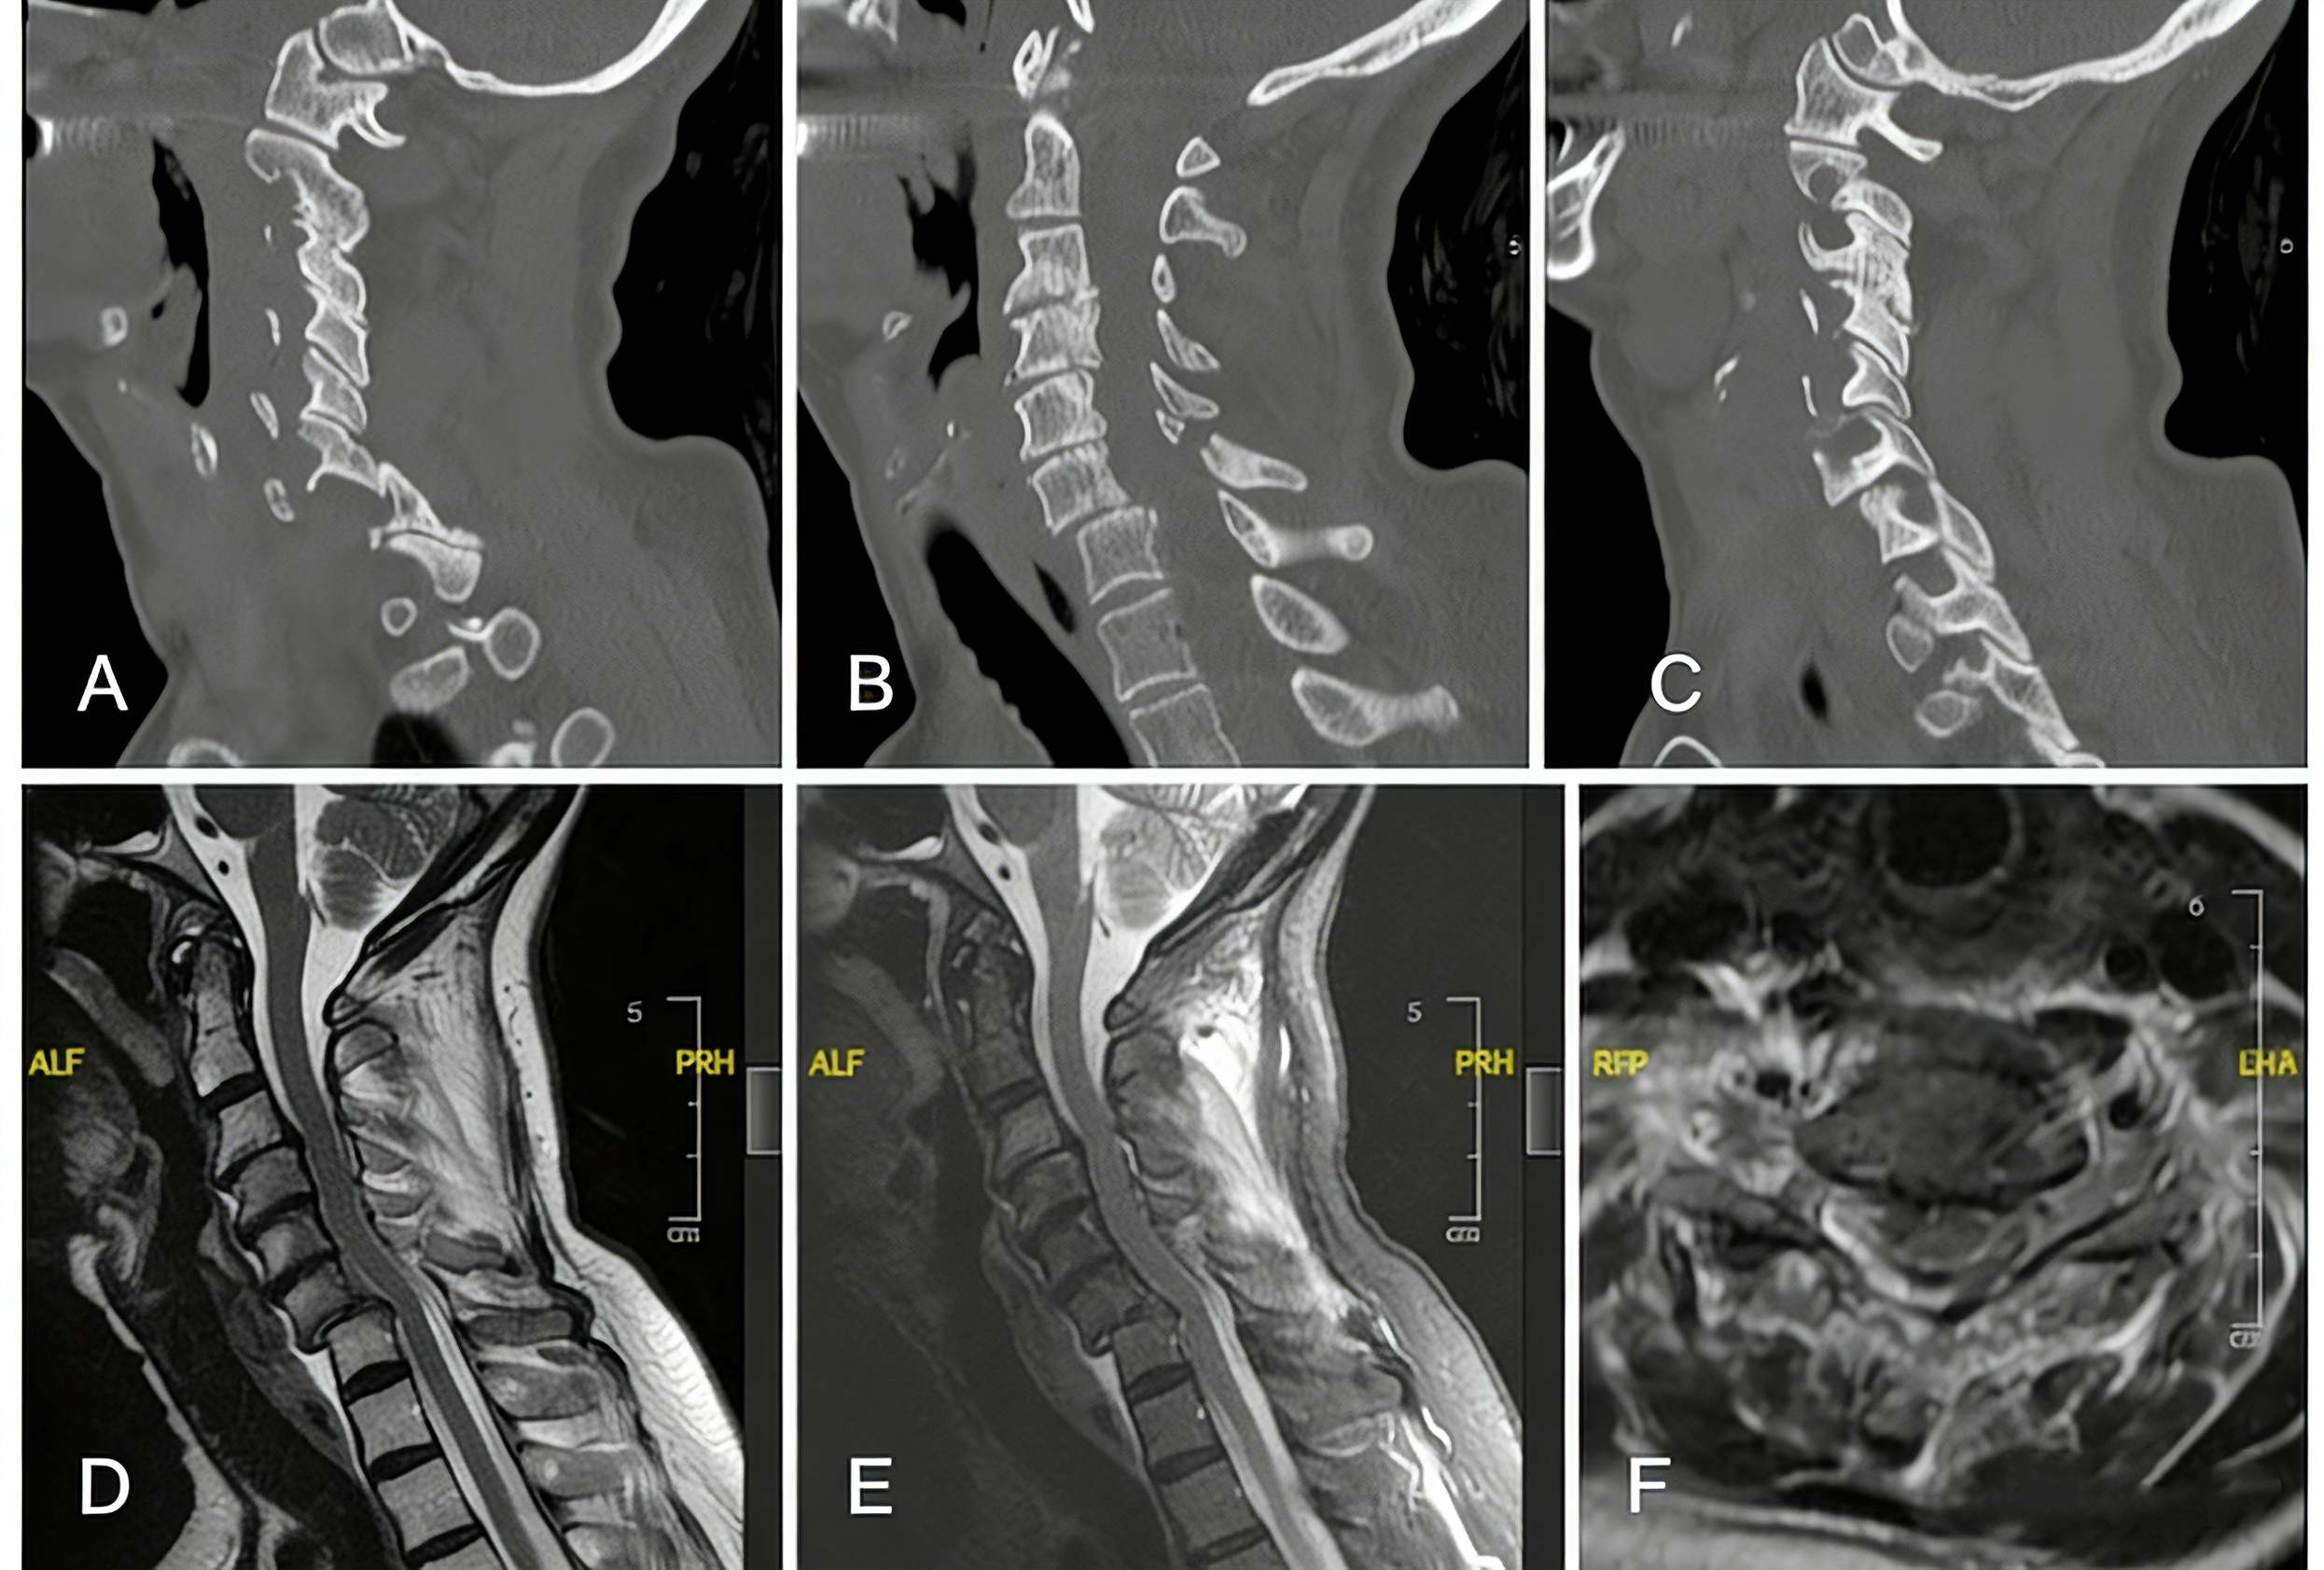

1_副本.jpg

Measurements of angle before (A) and after (B) the initial C6-7 ACDF surgery. Measurements of anterolisthesis on CT before surgical intervention (C) and after ACDF failure (D).